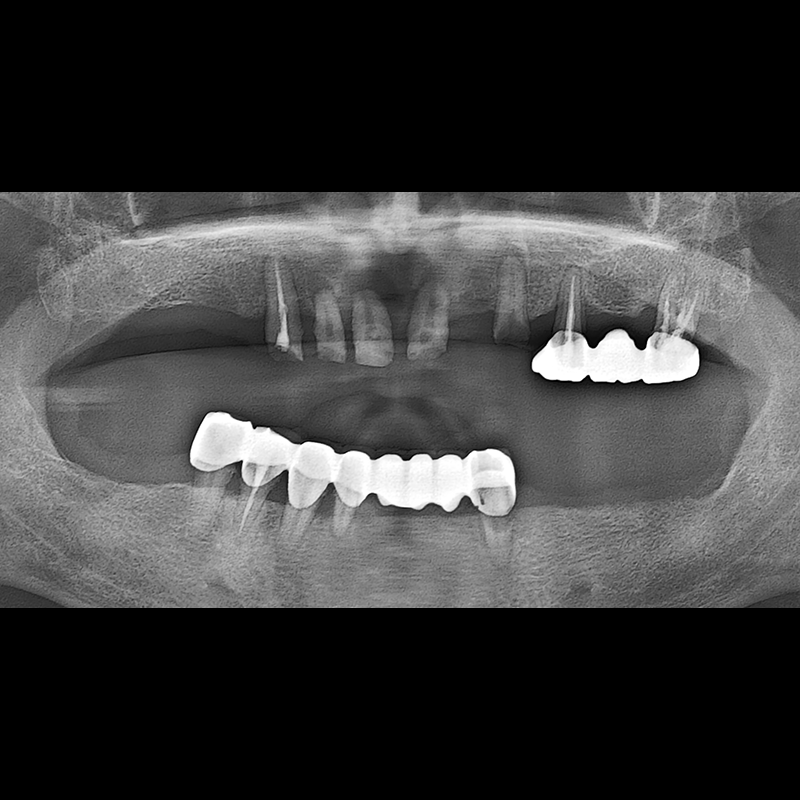

BEFORE AFTER

임플란트 전후사진 2025.05.30

결손된 치아 부분과 살리기 힘든 치아 위치에 임플란트를 식립하였습니다.